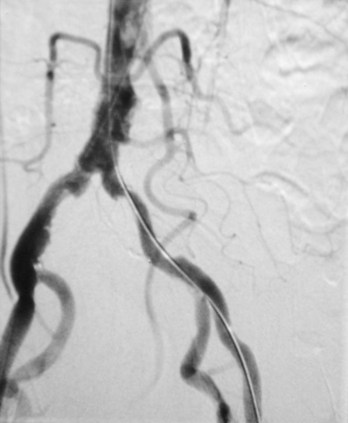

Subtraction angiography

During angiography it is often difficult to appreciate the contrast agent in the vessels through the overlying bony structures. To circumvent this, the technique of subtraction angiography has been developed. Simply, one or two images are obtained before the injection of contrast media. These images are inverted (such that a negative is created from the positive image). After injection of the contrast media into the vessels, a further series of images are obtained, demonstrating the passage of the contrast through the arteries into the veins and around the circulation. By adding the “negative precontrast image” to the positive postcontrast images, the bones and soft tissues are subtracted to produce a solitary image of contrast only. Before the advent of digital imaging this was a challenge, but now the use of computers has made this technique relatively straightforward and instantaneous (Fig. 1.5).

image

Fig. 1.5 Digital subtraction angiogram.